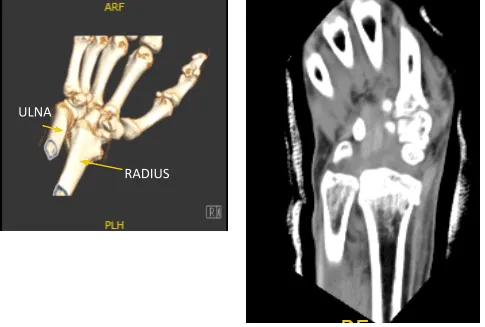

Xray were presented found comminuted impacted volarly angulated and volarly displaced intra-articular fracture of the distal radius. However, do not see any significant joint incongruity or step-off. There is ulnar plus variance. Minimally displaced fracture through the base of the ulna styloid. There is soft tissue swelling and joint effusion.